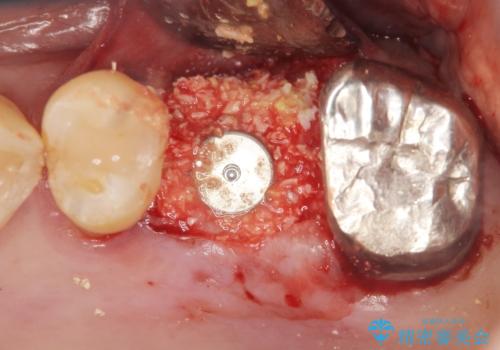

奥歯のインプラント ソケットリフト 60代男性

- 奥歯のインプラントをご希望し、来院された患者様です。

精査したところ上顎骨の厚みが薄かったため、ソケットリフト(上顎洞底挙上術)を併用してインプラント治療を行いました。

インプラントの種類:スプライン ツイスト (保証期間:5年)

クラウンの種類:ベレッツァクラウン (オールセラミック)

固定様式:セメント固定